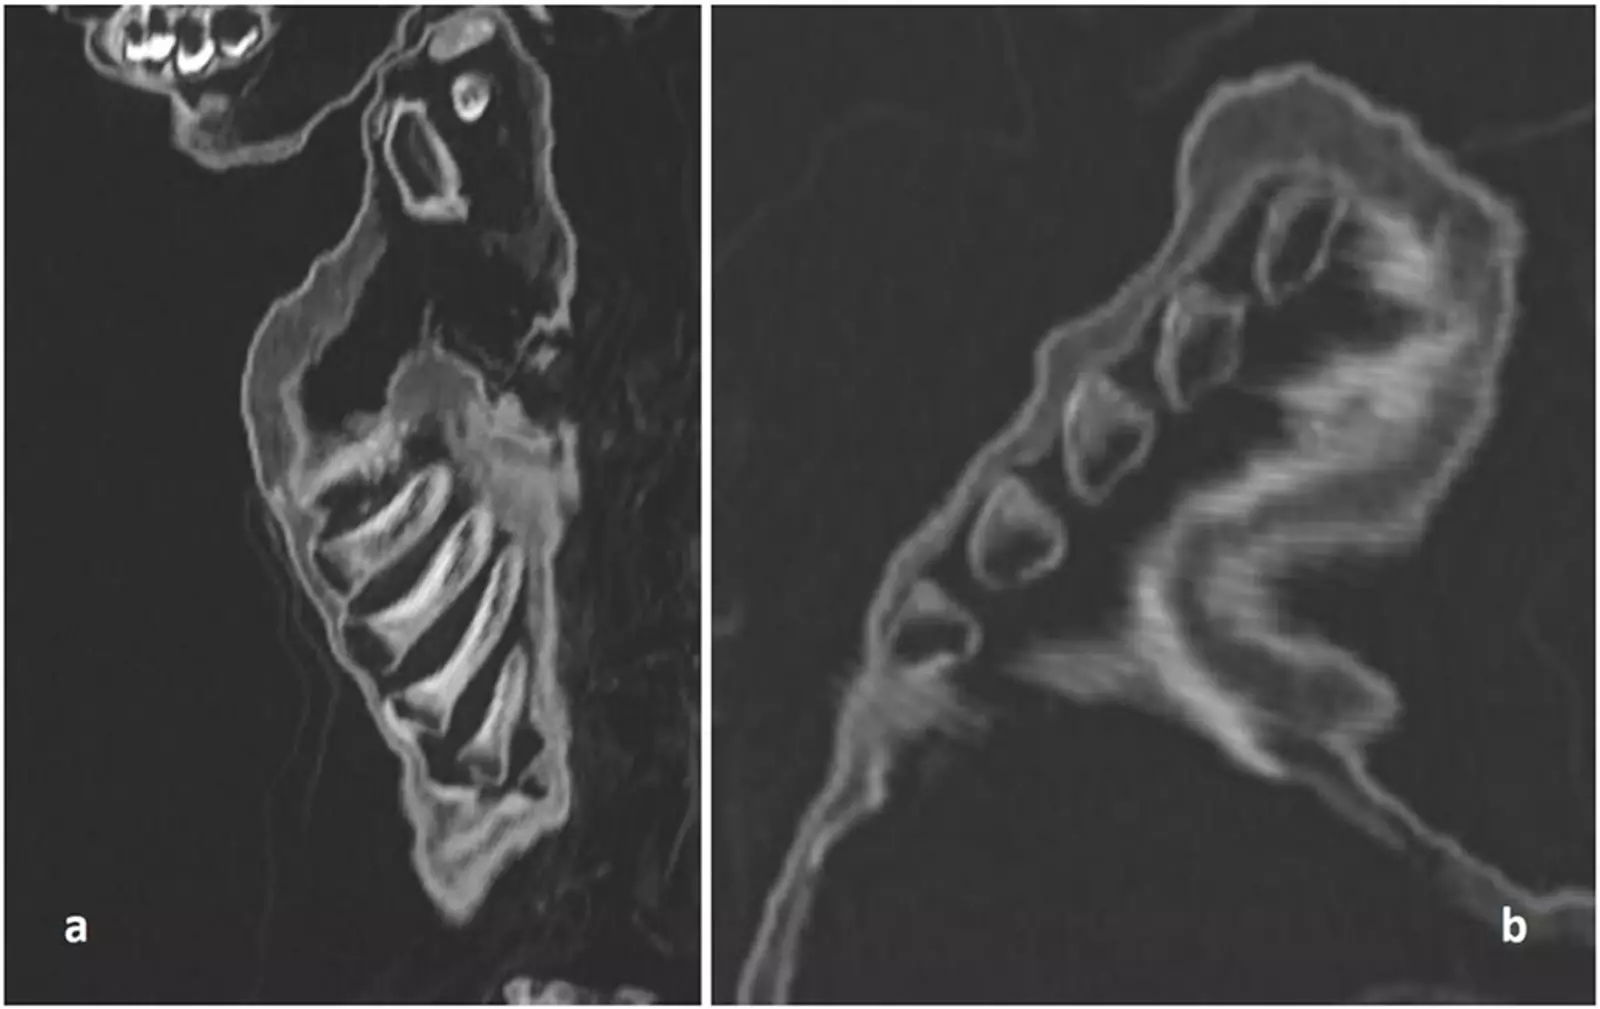

Основываясь на компьютерной томографии тела, команда подтвердила, что ребёнок был мальчиком, а размеры его костей и прорезывание зубов соответствовали годовалому возрасту. Сканирование реберных костей также выявило рахит, который возникает в первую очередь из-за недостатка солнечного света.

Виртуальное вскрытие выявило у ребёнка рахит и возможную цингу, - следствие острой нехватки витаминов.

Виртуальное вскрытие выявило у ребёнка рахит и возможную цингу — следствие острой нехватки витаминов.